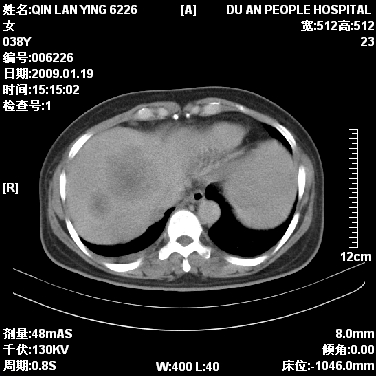

女,38岁,胸疼1个月。wbc:1万4

1)右肺中央型肺癌并右肺上叶阻塞性肺炎、节段性肺不张,纵隔淋巴结转移、右侧胸膜转移、肝脏转移。2)右侧胸腔少量积液。

1、右侧中央型肺癌并阻塞性肺不张,纵隔内、主动脉弓旁、右肺门淋巴结及肝脏转移可能性大,建议纤支镜进一步检查。

2、右侧胸腔积液。

本病例有几个容易诊断的地方:1、右肺上叶前段支气管闭塞,肺不张。2、淋巴结明显肿大。3、肝脏多个类圆形低密度影呈“牛眼征”改变,高度提示转移。

从影像学角度分析      右肺上叶中央型肺癌,并阻塞性不张、肺炎,纵隔淋巴结、膈顶淋巴结转移。

肝内两个大小不等低密度结节,内可见更低密度影,首先考虑肝内转移瘤,但联想到患者wbc1万4,建议楼主还是做个增强比较明确,除外肝脓肿的可能。